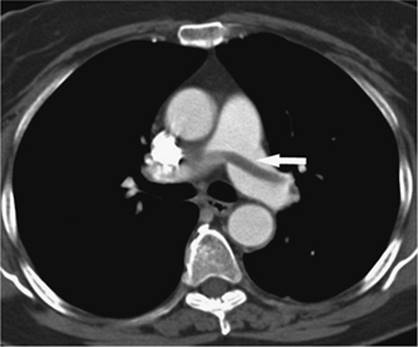

000450

Figure 35.20. Patient with cirrhosis undergoing a transjugular intrahepatic, portacaval shunting (TIPS) procedure. Catheter (white arrow) is positioned from a hepatic venous approach, through the hepatic parenchyma into the portal vein (black arrow). (Image courtesy of Harry K. Meisenbach, MD.)